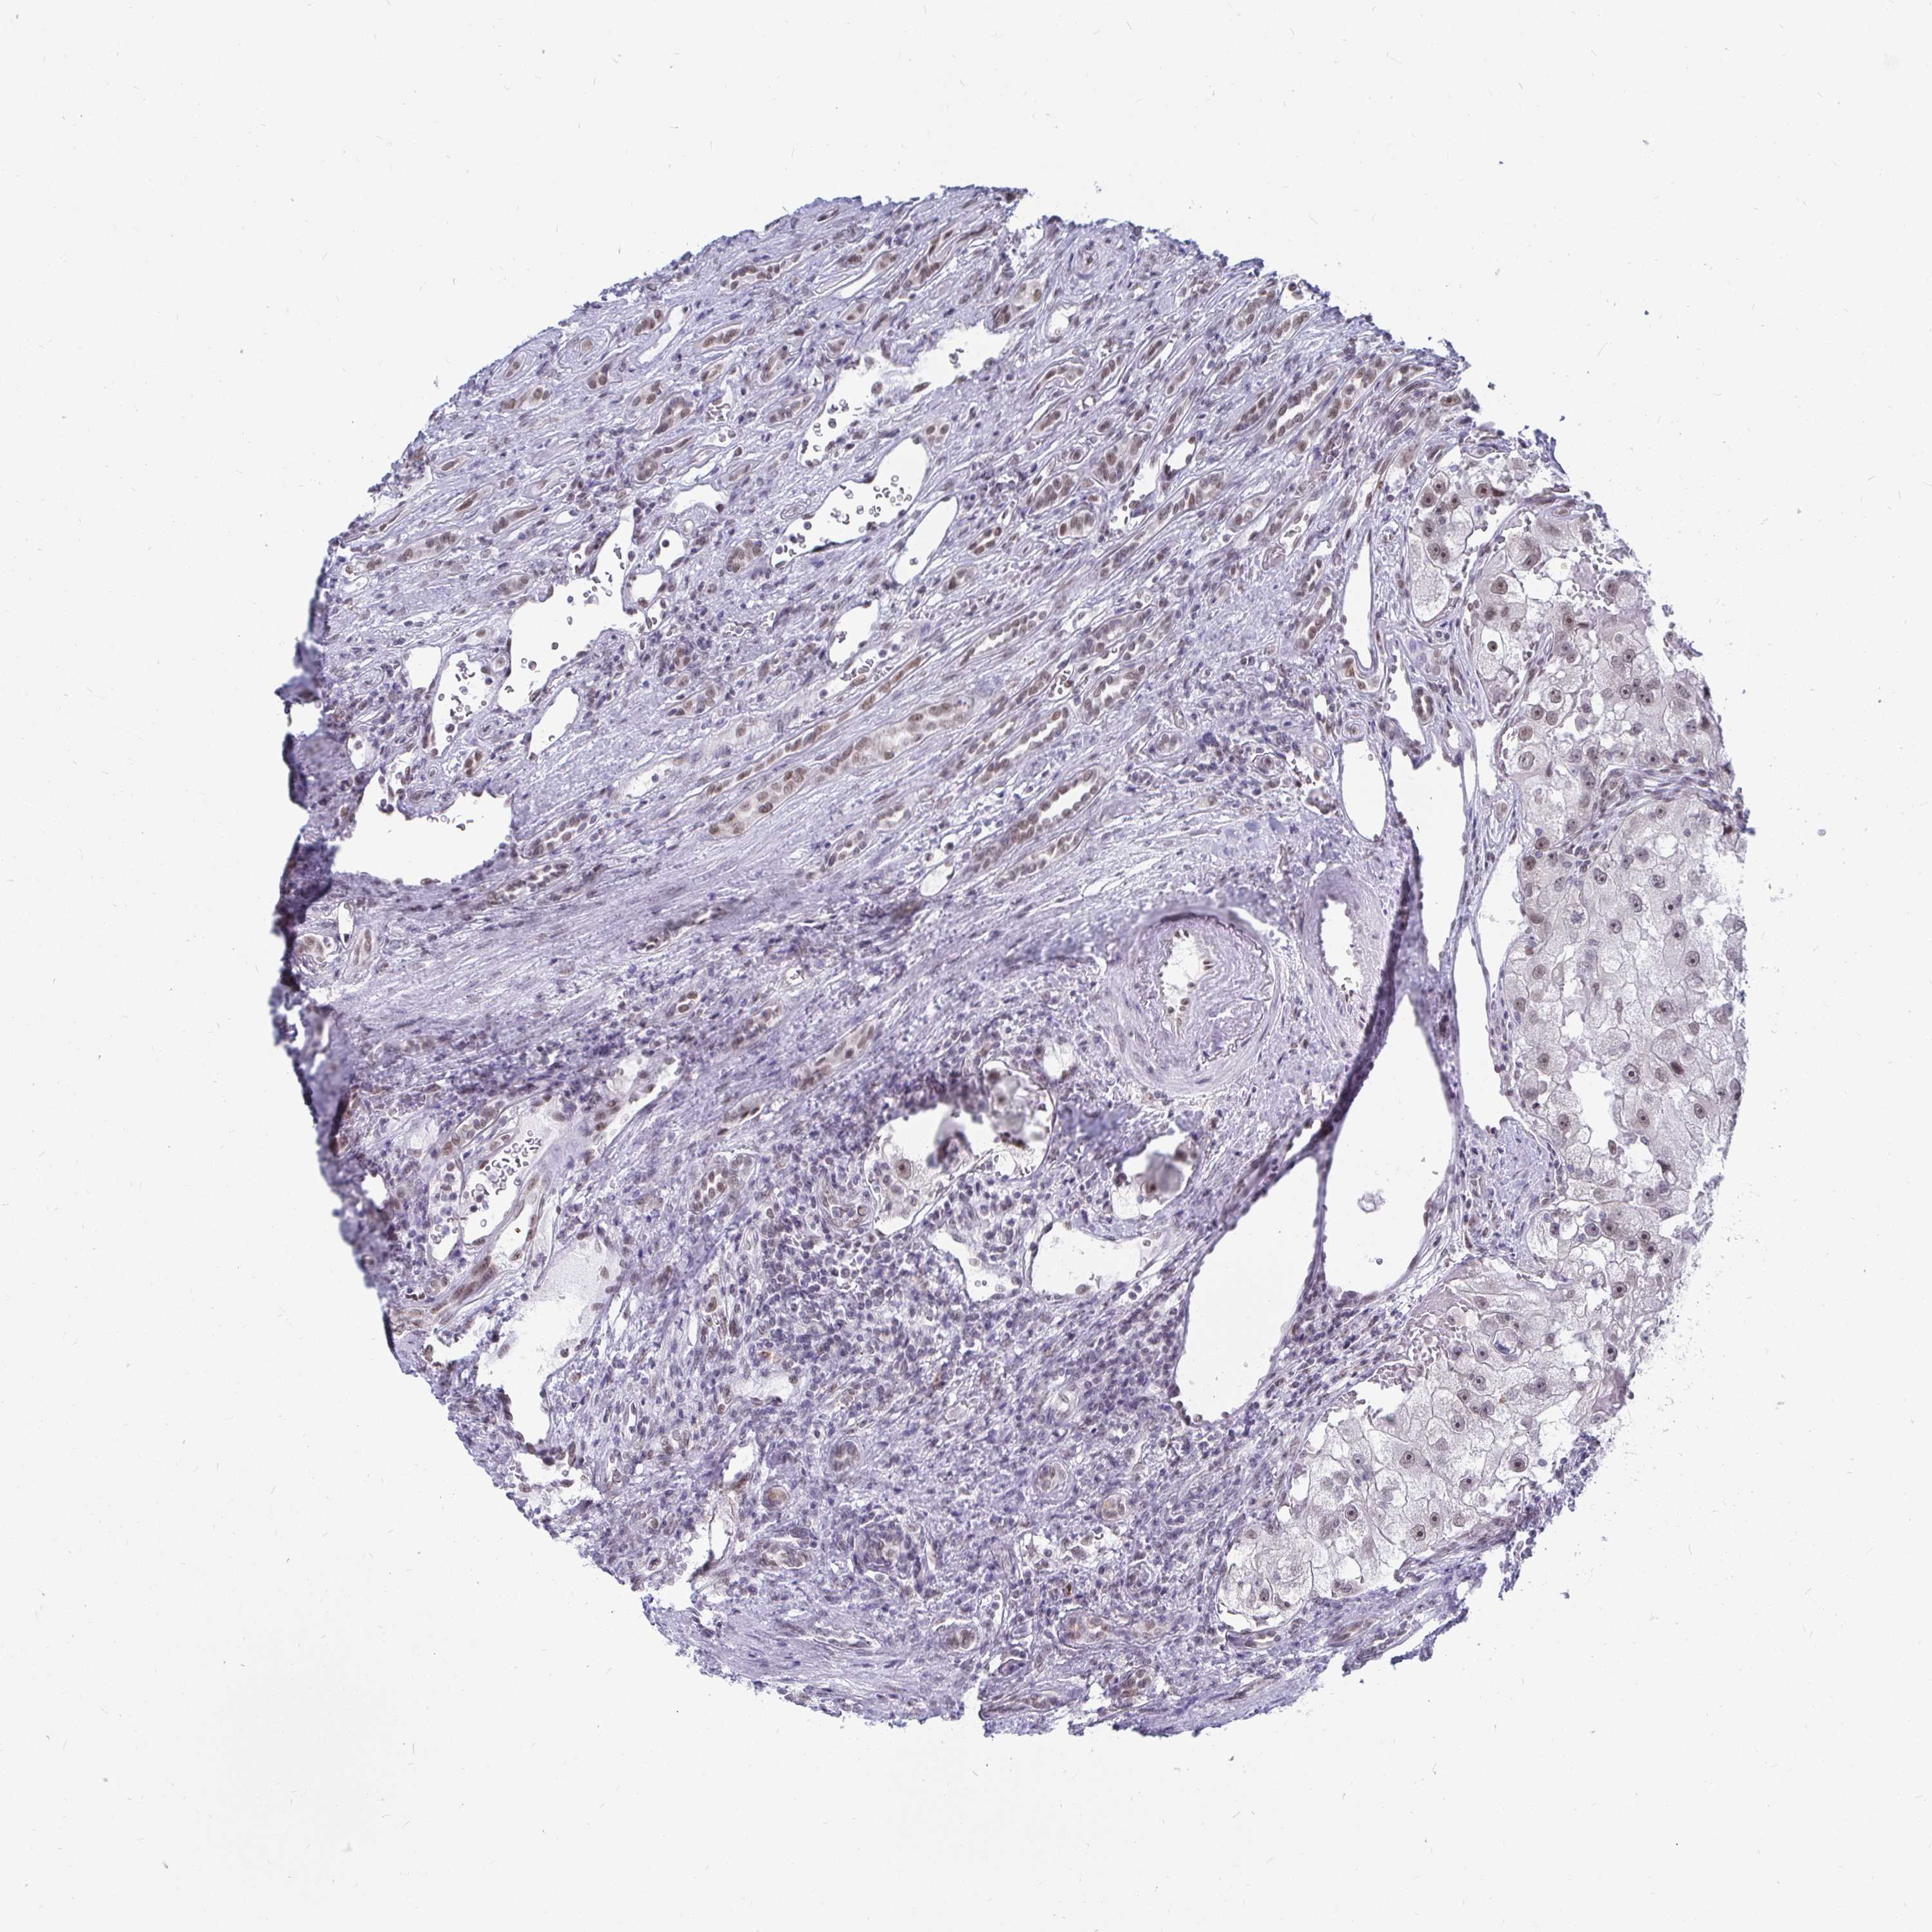

KIDNEY RENAL PAPILLARY CELL CARCINOMA (TCGA) - Interactive survival scatter ploti

The Survival Scatter plot shows the clinical status (i.e. dead or alive) for all individuals in the patient cohort, based on the same data that underlies the corresponding Kaplan-Meier plots. Patients that are alive at last time for follow-up are shown in blue and patients who have died during the study are shown in red.

The x-axis shows the expression levels (FPKM) of the investigated gene in the tumor tissue at the time of diagnosis. The y-axis shows the follow-up time after diagnosis (years). Both axes are complimented with kernel density curves demonstrating the data density over the axes. The top density plot shows the expression levels (FPKM) distribution among dead (red) and alive patients (blue). The right density plot shows the data density of the survived years of dead patients with high and low expression levels respectively, stratified using the cutoff indicated by the vertical dashed line through the Survival Scatter plot. This cutoff is automatically defined based on the FPKM cutoff that minimizes the p-score. The cutoff can be changed by dragging the vertical line or by entering a cutoff value in the square labeled "Current cut-off".

Under the Survival Scatter plot the p-score landscape (black curve; left axis) is shown together with dead median separation (red curve; right axis). Dead median separation is the difference in median mRNA expression between patients who have died with high and low expression, respectively. It is calculated as follows: median FPKM expression of dead patients with high expression - median FPKM expression of dead patients with low expression. This is intended to aid the user in visually exploring custom cutoffs and the associated p-scores and dead median separation.

Individual patient data is displayed and can be filtered by clicking on one or more of the category buttons on the top of the page. Categories describing expression level and patient information include: high, low, alive, dead, female, male and tumor stages. The scale of the x-axis can be toggled between linear and log-scale by clicking on the "x log" button. Mouse-over function shows TCGA ID, patient information and mRNA expression (FPKM) for each patient.

& Survival analysisi

Kaplan-Meier plots summarize results from analysis of correlation between mRNA expression level and patient survival. Patients were divided based on level of expression into one of the two groups "low" (under cut off) or "high" (over cut off). X-axis shows time for survival (years) and y-axis shows the probability of survival, where 1.0 corresponds to 100 percent.

TRIP12 is not prognostic in Kidney Renal Papillary Cell Carcinoma (TCGA)